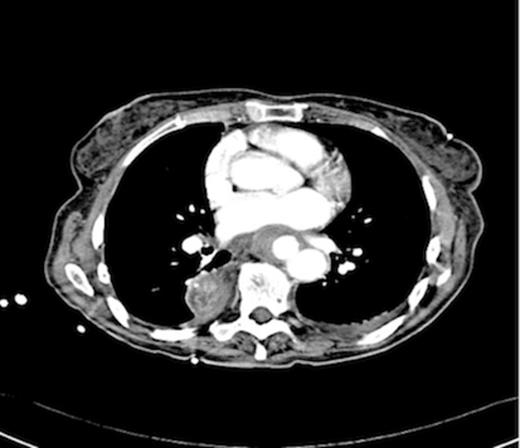

An endoscopy performed four years post-operatively demonstrated two atypical acute gastric ulcers in the distal stomach (figure 1), which were treated with a heat probe (figure 2). Two days later she presented as an emergency in hypovolaemic shock following a large volume haematemesis (haemoglobin of 40g/l). An urgent upper gastrointestinal endoscopy revealed a visible vessel at 35 cm forming part of an expansive mass within the gastric conduit. EUS demonstrated a heterogeneous mass indenting the gastric conduit, containing a strong Doppler signal (figure 3). An urgent computerised tomography (CT) angiogram revealed a Type-A thoracic aortic aneurysm with an enteric fistula (figure 4). The saccular aneurysm of the thoracic aorta was embedded in the gastric conduit. A 28x16cm Valiant® (Medtronic Ltd, Minneapolis, USA) stent was placed in the descending thoracic aorta with good occlusion of the aneurysm. The patient made an excellent recovery and was discharged on the seventh day post stenting.